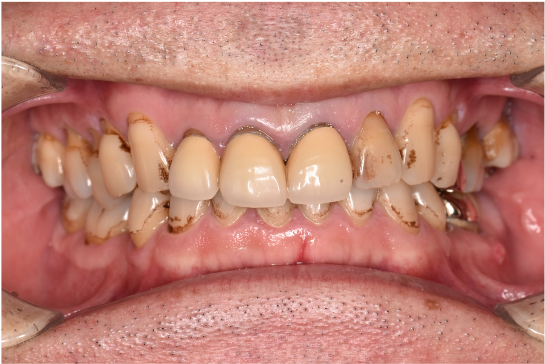

治療前

| ご相談内容 | 「歯についた黒ずみが気になる 5年程歯科に行っていないため、しっかりクリーニングを受けたい」とご相談をいただきました。 |

| カウンセリング・診断結果 | ご相談通り、全体的に着色と歯石が付着していました。歯周病の検査を行ったところ全体的に歯周病が進行しており、中等度~重度の歯周炎が認められました。 |

| 行ったご提案・治療内容 | 初診時に撮影したレントゲン、口腔内写真、歯周検査の結果を用いて、着色除去、歯周病治療の必要性をお伝えしました。 初診時は歯ブラシのお話しをさせていただき、セルフケアの方法について説明を行い、その後気にされてみえた着色除去、歯肉縁上歯石除去を行いましました。 歯肉の炎症がある程度落ち着いたところで、後日、再評価を行い歯周治療へ移行しました。 |